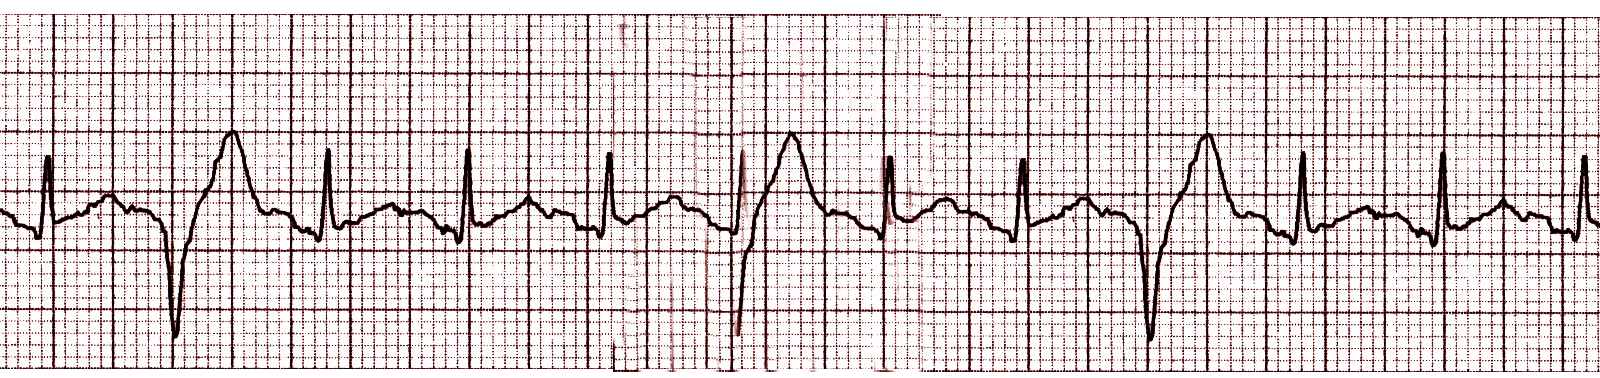

Question 10 of 34

10. Question

Name that rhythm -